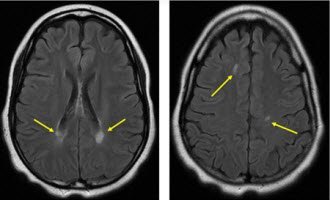

В ходе исследования МРТ обнаруживаются крупные субкортикальные (подкорковые) очаги – гиперинтенсивные (режим Т2) и гипоинтенсивные (режим Т1).

Исследование КТ показывает двухсторонний лейкоареоз – малую ишемию сосудов, повреждения элементов сосудистой системы белого вещества. При перивентрикулярной лейкоэнцефалопатии на МР-томограмме различается диффузно-очаговое поражение белого вещества преимущественно симметричное.

Для сравнения при вирусном поражении очаги расположены преимущественно ассиметрично. Единичный неспецифический очаг лейкоэнцефалопатии может быть ошибочно расценен, как проявление инсульта.

- магнитно-резонансная томография – МР картина сосудистой лейкоэнцефалопатии представляется множеством мелких очагов поражения;

На МРТ обнаруживаются очаги повышенной интенсивности, располагающиеся асимметрично в области белого вещества лобных и затылочных долей. МР картина перивентрикулярной мелкоочаговой лейкоэнцефалопатии: на Т1 режиме очаги низкой интенсивности. Очаги также обнаруживаются в коре головного мозга, стволовых отделах и мозжечке.